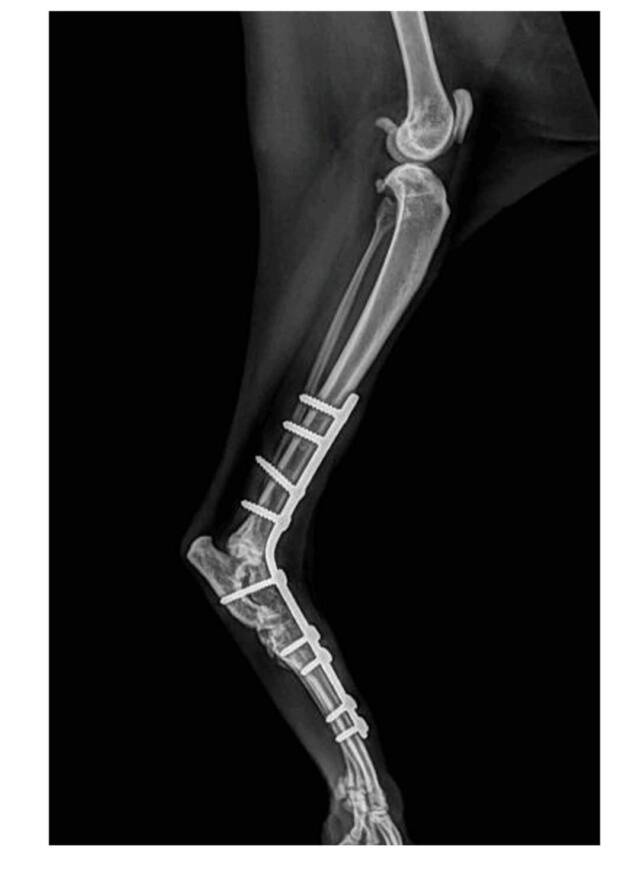

Brisa is in 2022 uit de kennel gehaald, Brisa had haar poot flink kapot en is hier aan geopereerd. Helaas bleek de operatie niet afdoende en Brisa heeft altijd last van de poot gehouden en kan hem niet goed het belasten. Hiervoor krijgt ze revalidatie en dit werkt goed voor deze mooie dame.

Brisa heeft revalidatie nodig, niet dat ze ooit weer gaat bewegen en lopen als een normal kat maar het houdt de spieren soepel waardoor haar bewegingen verbeteren en het neemt de pijn weg.

Brisa heeft per jaar ongeveer 2x een sessie reeks nodig van 10 behandelingen, in totaal dus iets van 20 sessies. Dit is niet goedkoop maar het verbeterd en dan ook veel haar mobiltiet en misschien nog wel belangrijker het neemt die pijn weg die ontstaat door overbelasting aan de voorpoten.

Een sessie reeks van 10 stuks kost 615 euro, per jaar heeft Brisa dus 1230 euro nodig voor de revalidatie.